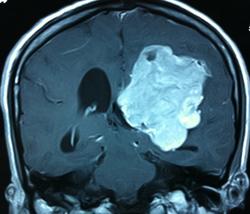

Начало вот здесь http://www.radiomed.ru/cases/kt-gms-obemnoe-obrazovanie-levoi-gemisfery-bolshogo-mozga-vnutrizheludochkovaya-meningioma. Пациент оперирован (меня сначала дезинформировали по поводу операции), перед операцией состояние ухудшилось, возникла правосторонняя гемиплегия, которая осталась и после декомпрессии. МРТ, КТ снимки и выписку предоставила супруга пациента, снимал на iphone, простите за качество, дисков с исследованиями не записывали. Надеюсь вопрос по данному случаю исчерпан.

Вот "цветочки":

T1+C

И Вы считаете, что эта опухоль имеет интравентрикулярную локализацию?

Изначально по КТ я так предпологал, а теперь на 100% уверен, разве МРТ это не показало? Гистологически - менингиома, опухоль мозговой оболочки. Покажите, пожалуйста, образование где-нибудь прилежит к костям, где есть мозговая оболочка? Я не вижу, зато отчетливо вижу в левом боковом желудочке из оболочек сосудистого сплетения. Что вас еще смущает? По-моему, предостаточно фактов, чтобы развеять все сомнения.

Мне видится так. Иначе в данной локализации просто неоткуда расти оболочечной опухоли. На контрольной КТ, после декомпрессии, когда срединные структуры стали действительно срединны, правое обызвествленное сосудистое сплетение видно отчетливо, а левое, где оно? Ведь если бы образование компремировало, то после операции, когда часть мозга пролабировало в трепанационное отверстие мы бы увидели и левое сосудистое сплетение, но оно интимно связано с образованием и даже "потянулось" за ним в сторону декомпрессионного отверстия, потому что это и есть "росток" откуда выросла опухоль.